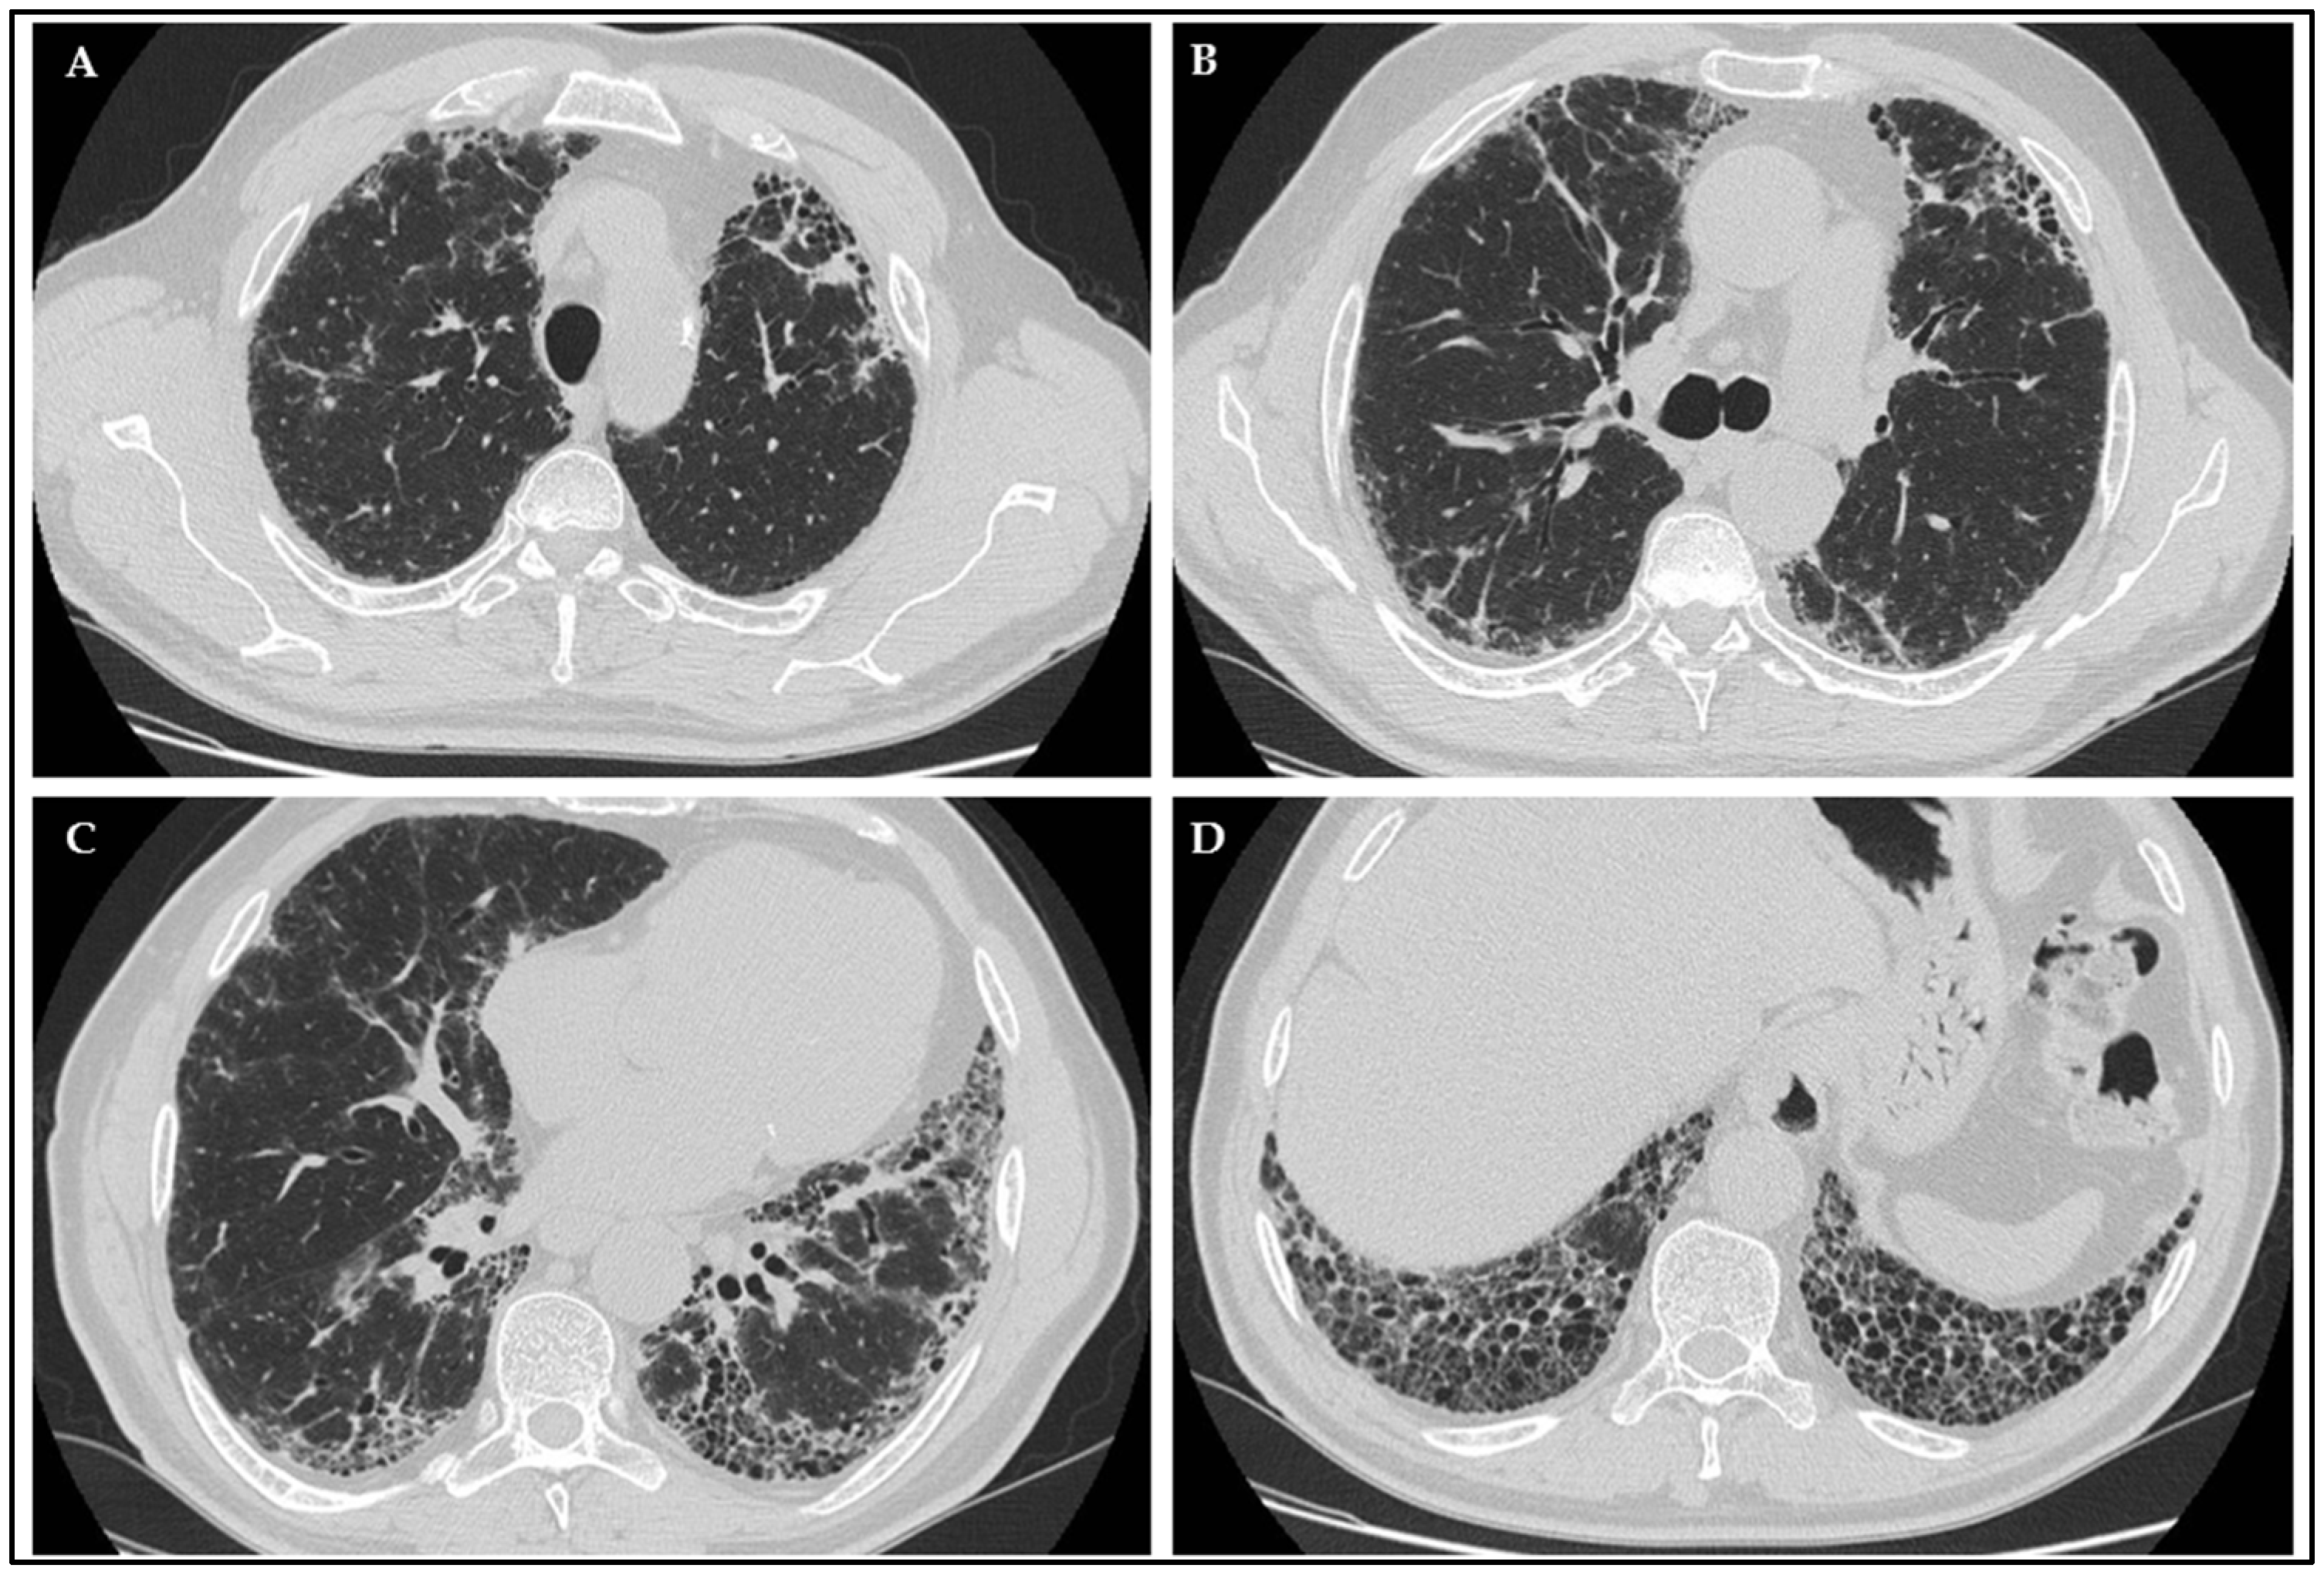

2.6. Radiological Evaluation